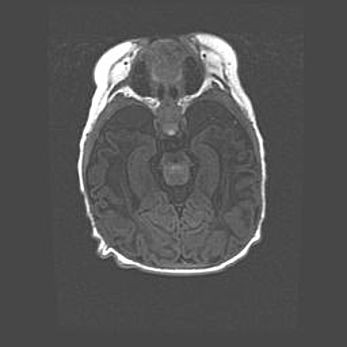

Церебральная ишемия II.

Возраст: 5 дней

Вес: 3400 г

Пол: женский

Окружность головы: 35 см

Срок гестации: 39 недель

Церебральная ишемия – это заболевание, характеризующееся недостаточностью (гипоксией) либо полным прекращением (аноксией) снабжения мозга кислородом по причине закупорки одного или нескольких сосудов. Это приводит к  что метаболическим расстройствам различной степени тяжести в тканях головного мозга, развитию коагуляционных некрозов и гибели нейронов.